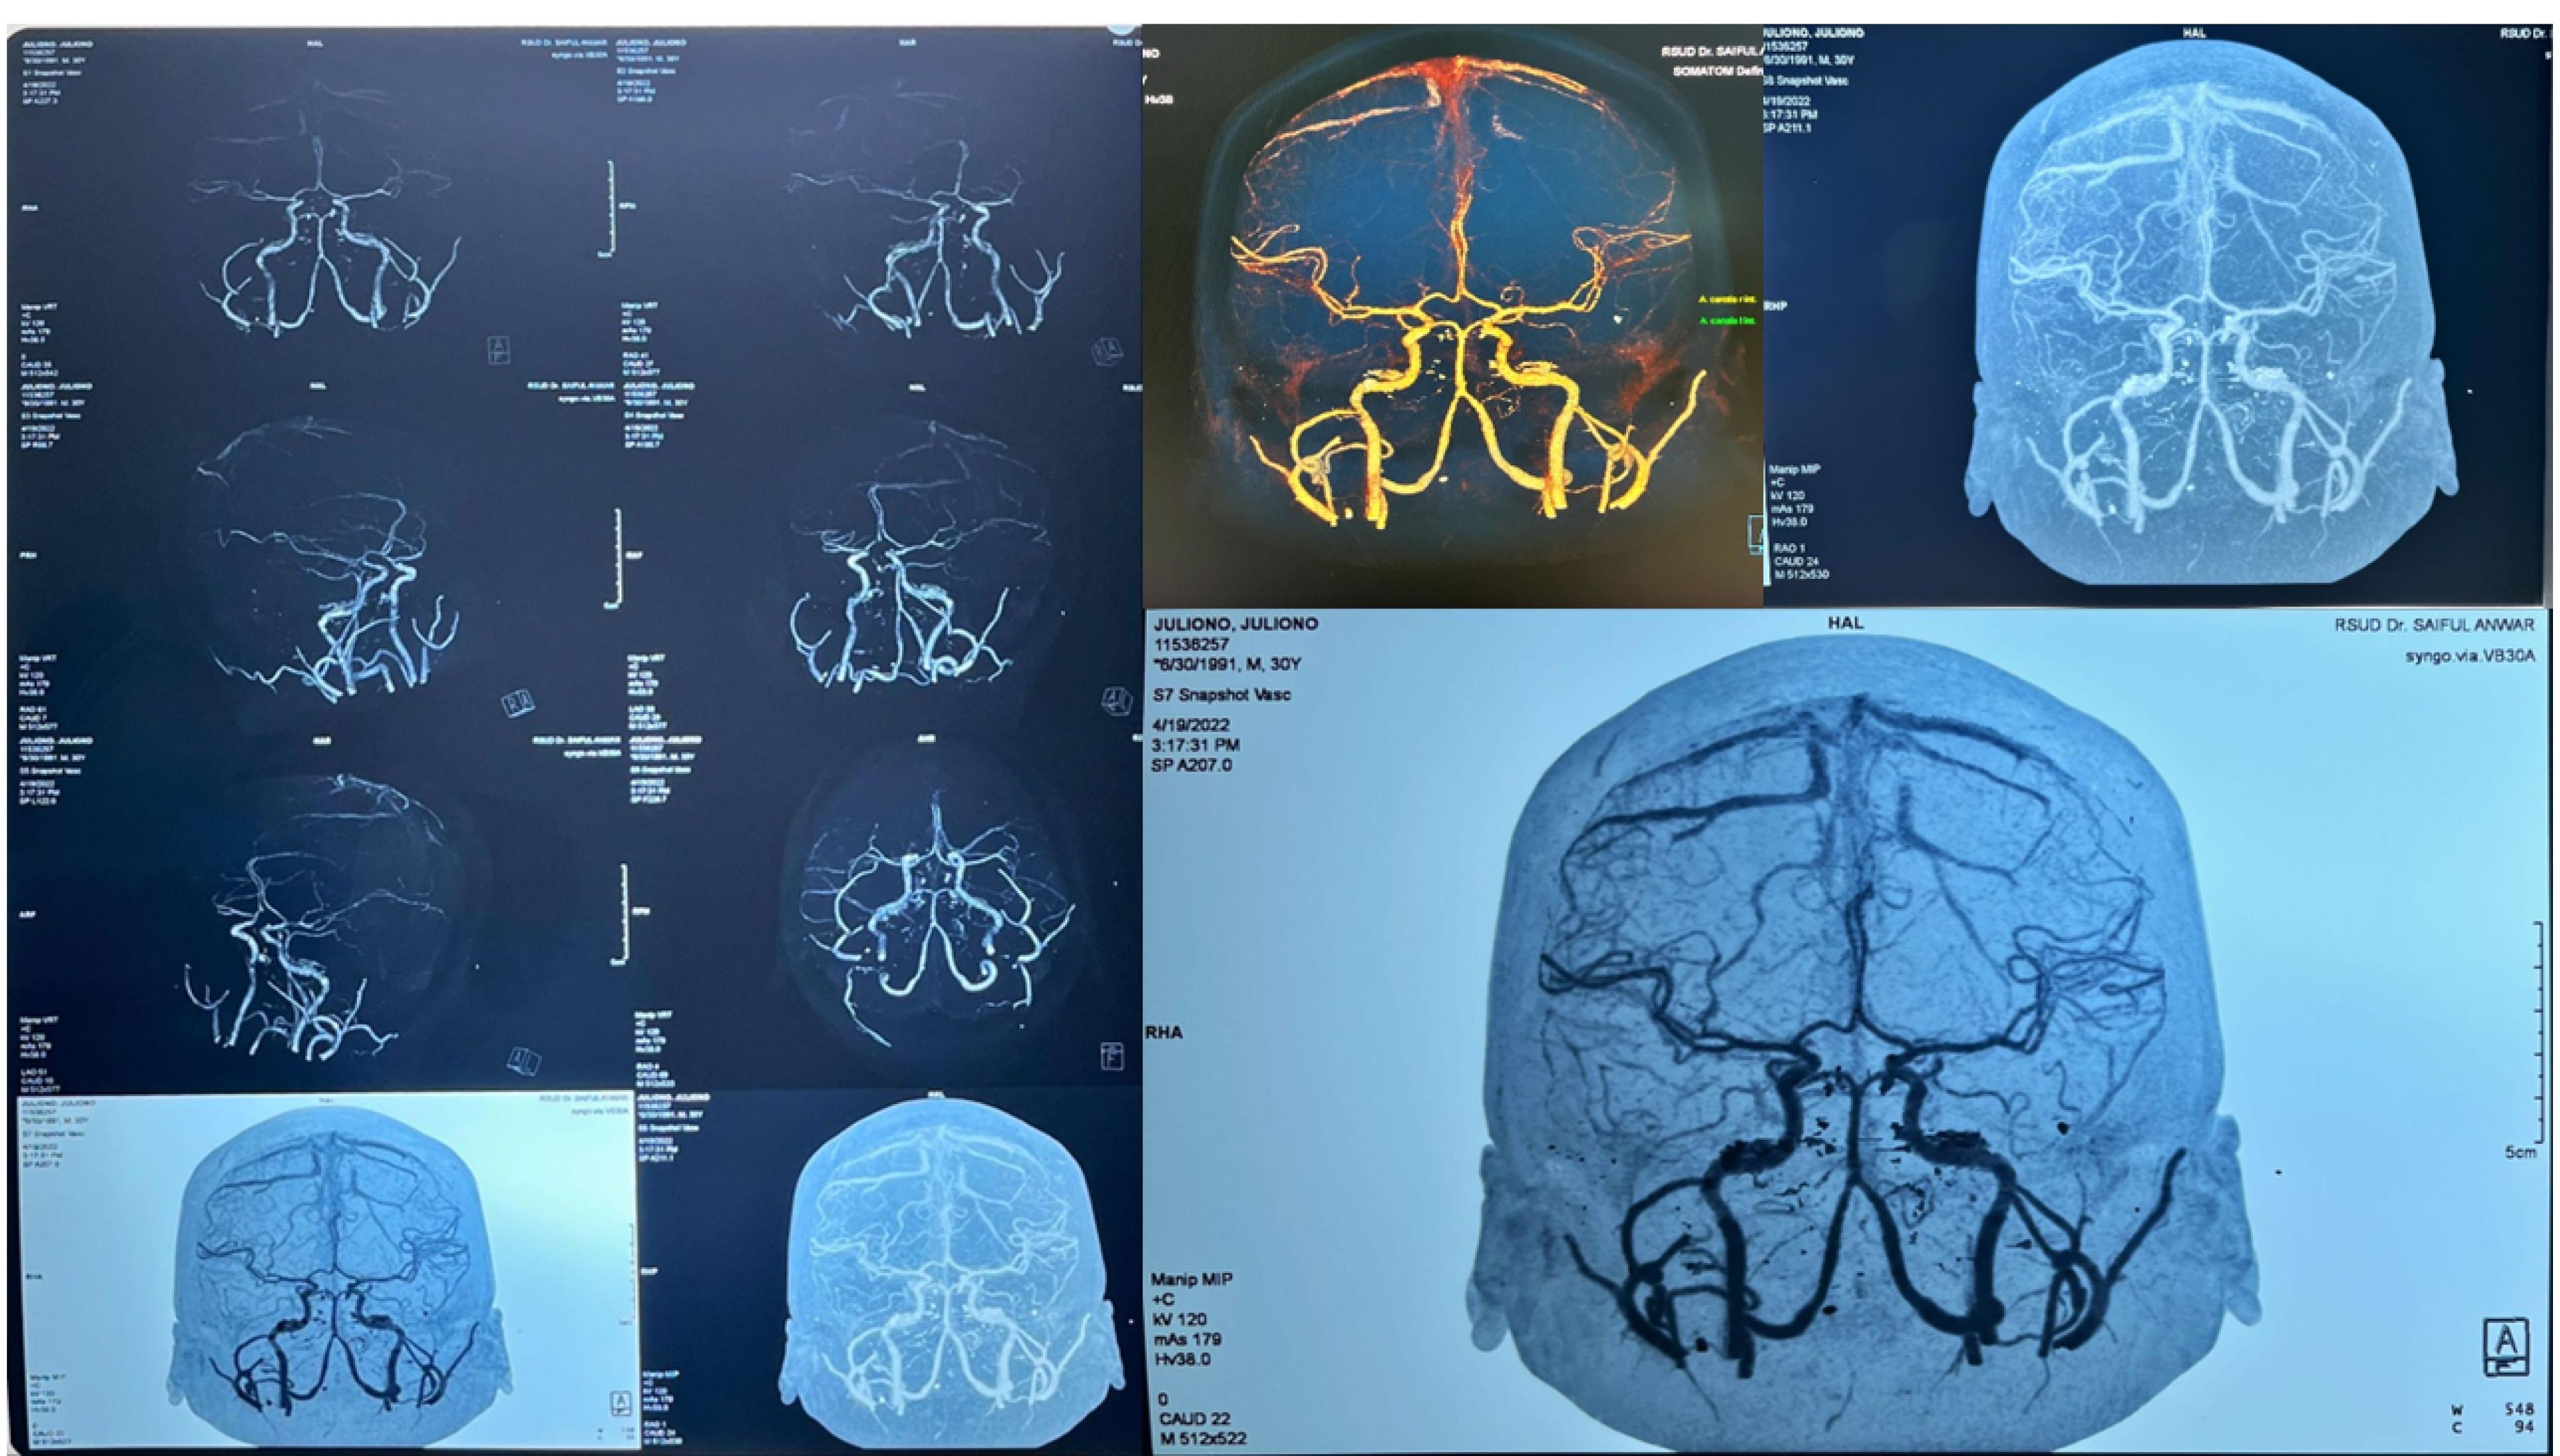

Figure 2.

Head CT scan examination ICH frontoparietal

The result of diagnosis stated that the patient had convulsion, CVA ICH frontoparietal D vol 18 cc and stage I hypertension. There was no aneurism or AVM (Figure 3). All procedures performed in this study were in accordance with the ethical standards of the institutional and/or national research committee.

Figure 3.

Head CT angiography